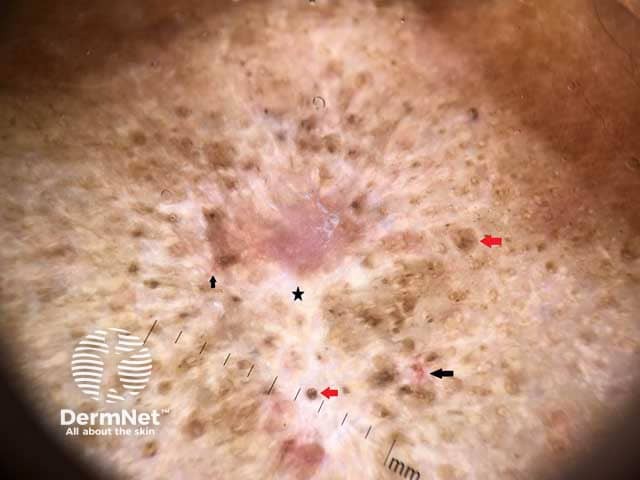

White area (black star), follicular plugs (red arrows), telangiectasia (black arrows)